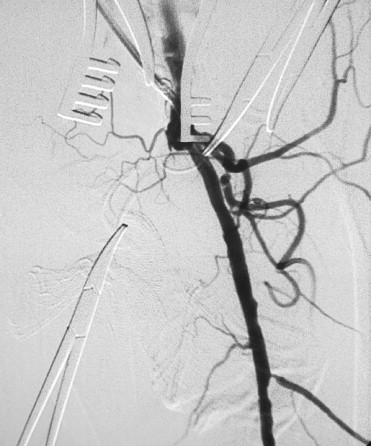

Among the patients with CLI who were admitted to our hospital after September 2007, 46 patients had chronic full-length occlusion of the SFA involving its ostium and at least one patent crural artery in the angiographical assessment. Even in the oblique lateral angiogram, the SFA was occluded with no proximal stump (Fig. 1). The status of the popliteal artery was not discussed in regard to patient enrollment because it is difficult to precisely define the boundary between the SFA and the popliteal artery in the angiography of the occlusive infrainguinal artery. Nevertheless, these lesions were classified as Trans-Atlantic Inter-Society Consensus (TASC)-II D lesion.2 Of these 46 patients, 10 elderly patients (11 limbs) were judged to have a restricted daily activity as already been mentioned above and therefore were enrolled in our study (Table 1). Case 4 is the contralateral limb of Case 3 in the same patient. These patients were all males with a mean age of 84.1 ± 5.4 years. The comorbidities included cardiac diseases in all patients, cerebral vascular diseases in four patients, and renal failure in one patient. Diabetes mellitus was present in three patients. The indication for the management was pain at rest in three limbs in two patients (Cases 3, 4, and 9), and tissue loss or minor gangrene in eight limbs in the other cases. In two cases, iliac steno-obstructive lesions had been already managed by EVT, but CLI due to the infrainguinal lesion remained.

The condition of the ostium of the superficial femoral artery confirmed by the ...

Figure 1.

The condition of the ostium of the superficial femoral artery confirmed by the lateral oblique view.